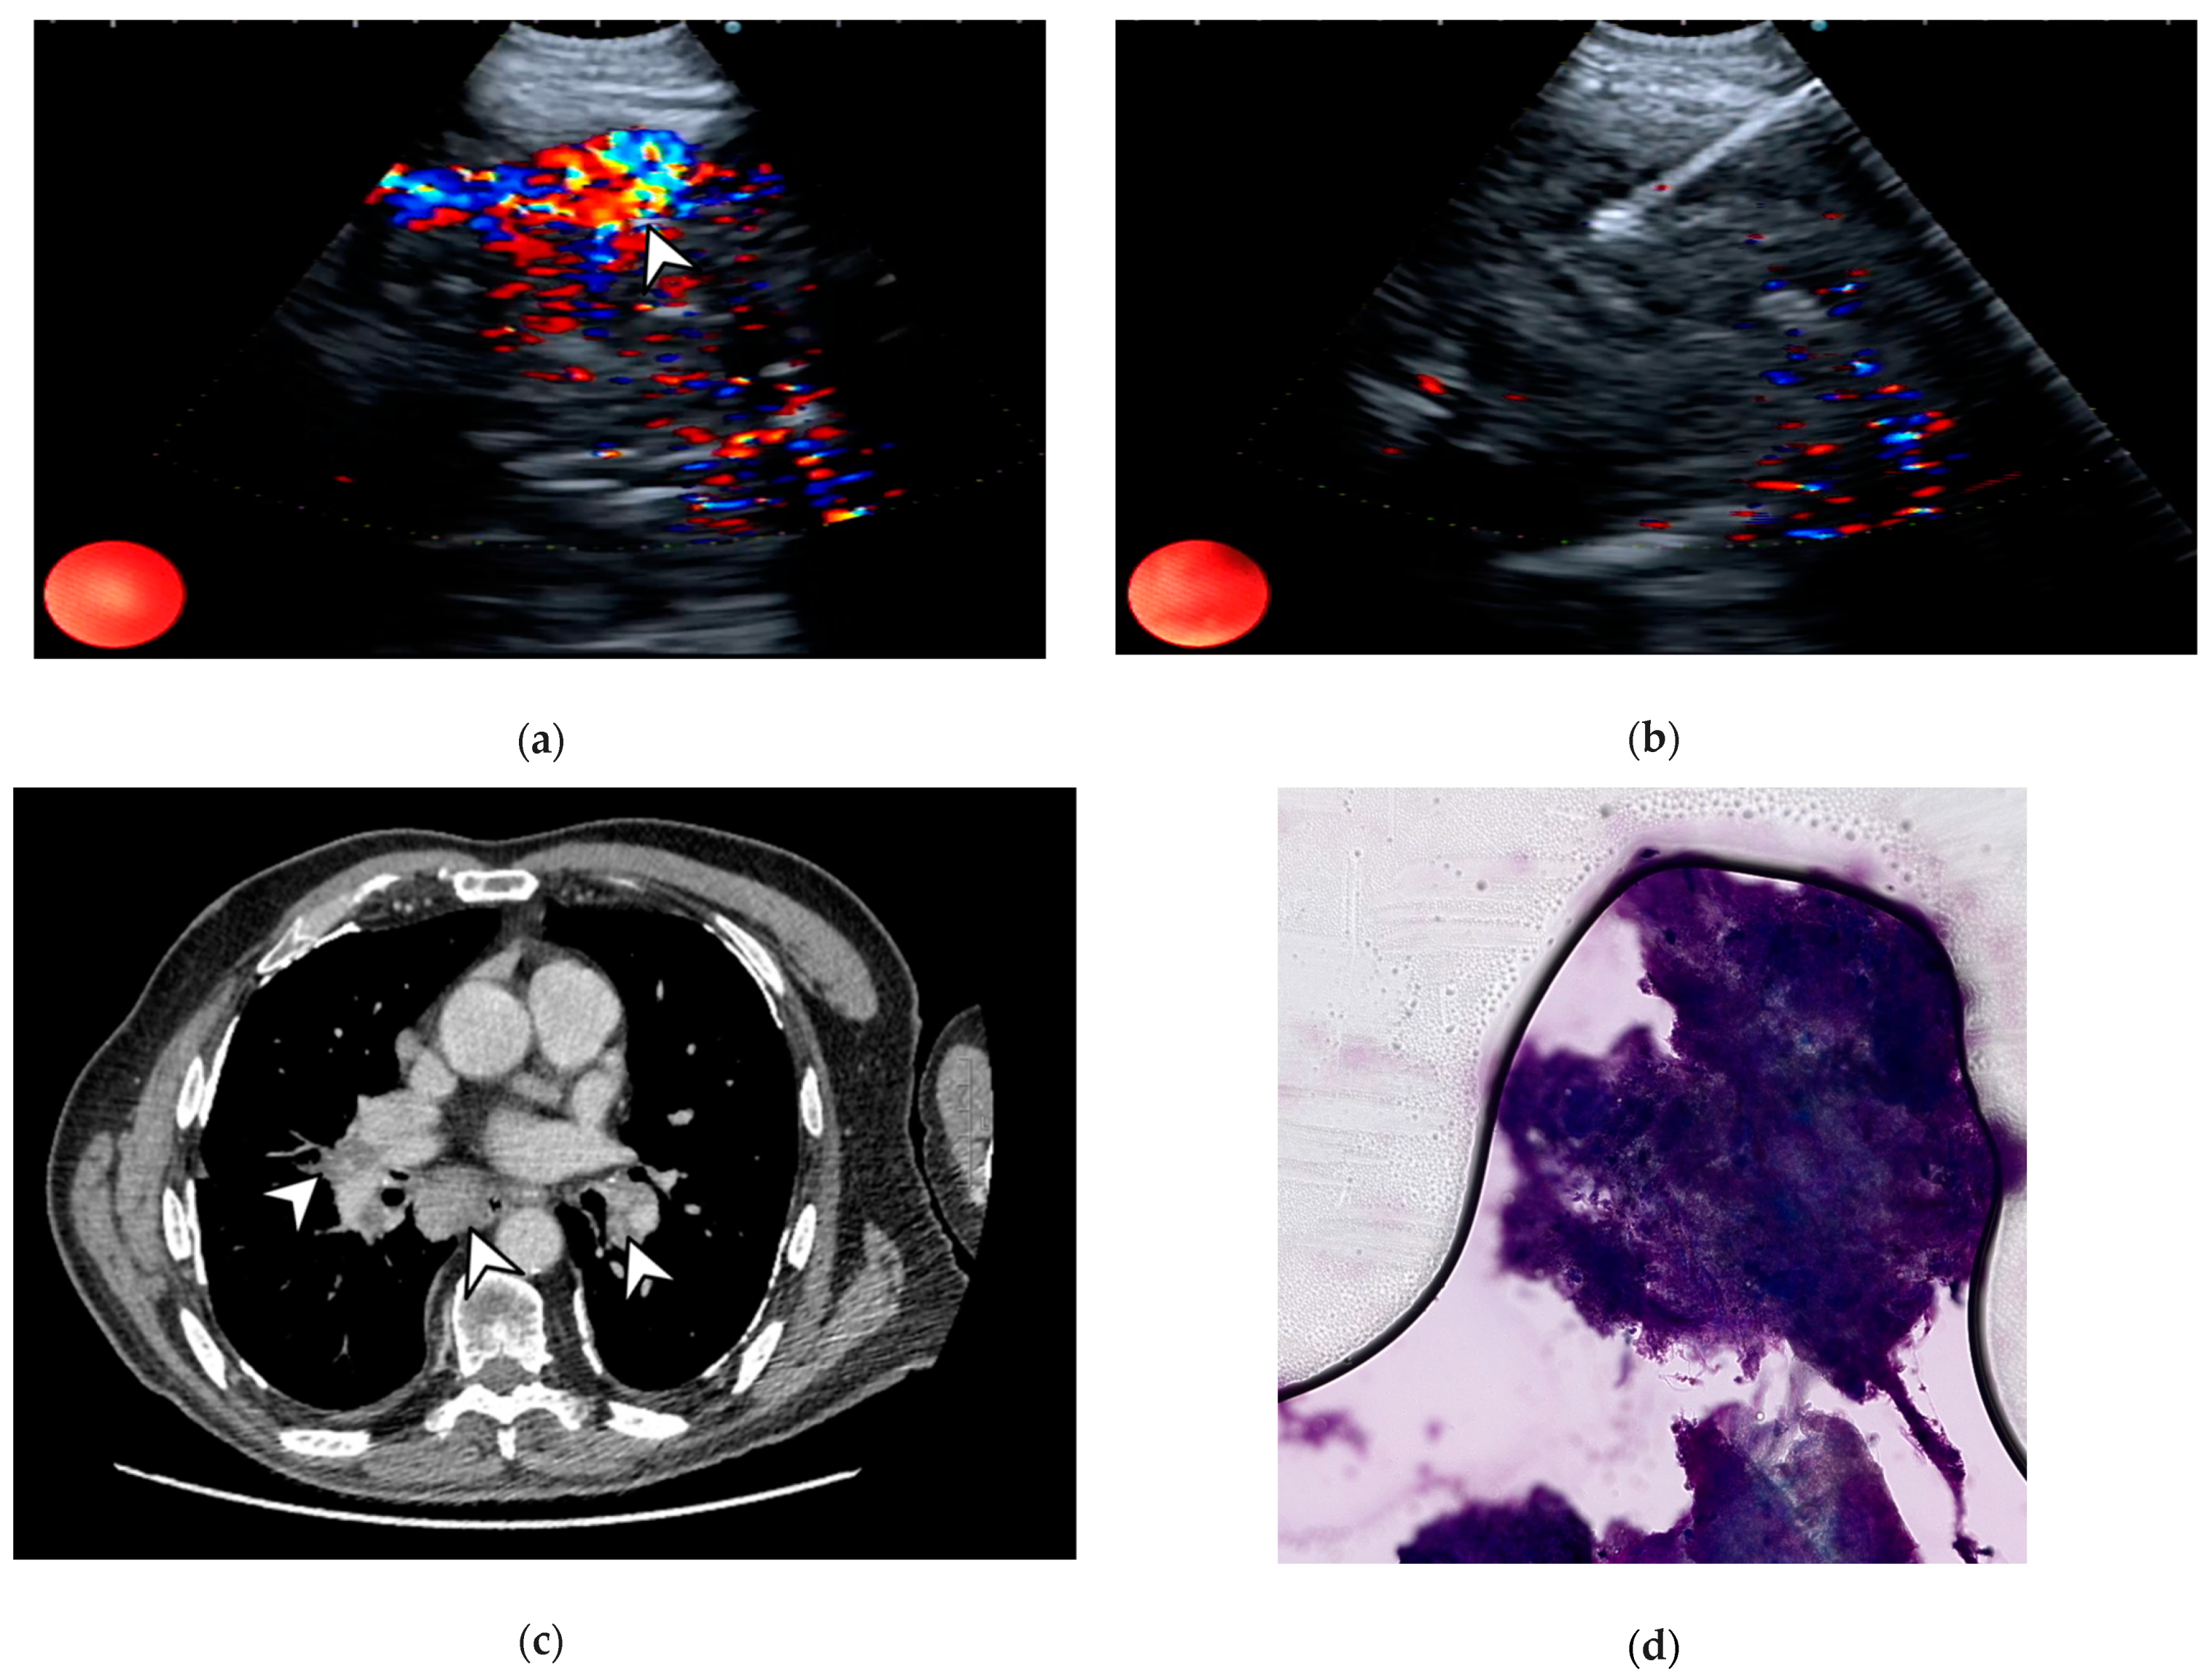

4.4. Color Doppler

- Nakajima, T.; Anayama, T.; Shingyoji, M.; Kimura, H.; Yoshino, I.; Yasufuku, K. Vascular Image Patterns of Lymph Nodes for the Prediction of Metastatic Disease During EBUS-TBNA for Mediastinal Staging of Lung Cancer. J. Thorac. Oncol. 2012, 7, 1009–1014. [Google Scholar] [CrossRef] [PubMed]

- Nosotti, M.; Palleschi, A.; Tosi, D.; Mendogni, P.; Righi, I.; Carrinola, R.; Rosso, L. Color-Doppler Sonography Patterns in Endobronchial Ultrasound-Guided Transbronchial Needle Aspiration of Mediastinal Lymph-Nodes. J. Thorac. Dis. 2017, 9, S376–S380. [Google Scholar] [CrossRef] [PubMed][Green Version]

6.7. Image-Guided Percutaneous Transthoracic Needle Biopsy (PTNB)

7. Rapid On-Site Evaluation (ROSE)